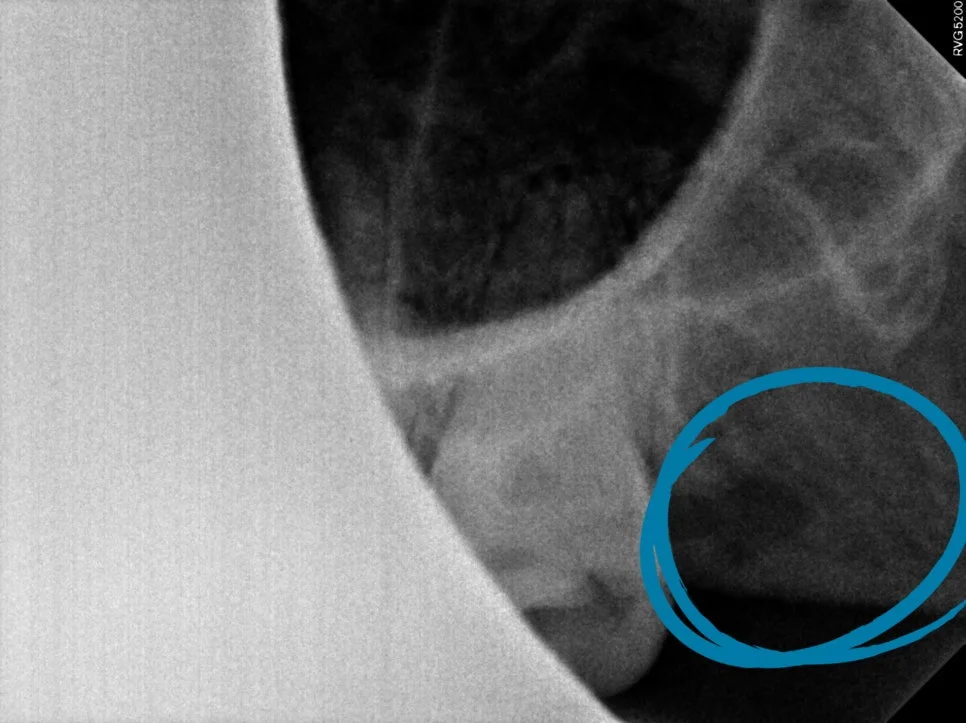

CBCT 진단 — 신경관 위치 사전 확인

CT를 보면 사랑니가 신경관과 꽤나 가까이 맞닿아 있는 상태가 확인되었습니다.

이런 경우에는 CT 검사가 선택이 아니라 필요한 과정인데요. 정확한 영상을 통해 발치 동선을 사전에 계획할 수 있어 신경 손상과 같은 위험 요소를 대폭 줄일 수 있습니다.

사랑니가 신경관에 가까울수록 하치조신경 손상 위험이 있기 때문에 사전 CBCT(3D CT) 검사가 필수입니다. 정확한 영상을 통해 발치 동선을 사전에 계획할 수 있어 신경 손상 위험을 대폭 줄일 수 있습니다. 서울쏙쏙치과에서는 CT를 통해 신경관 위치를 확인한 후 안전한 경로를 설계하여 발치합니다.